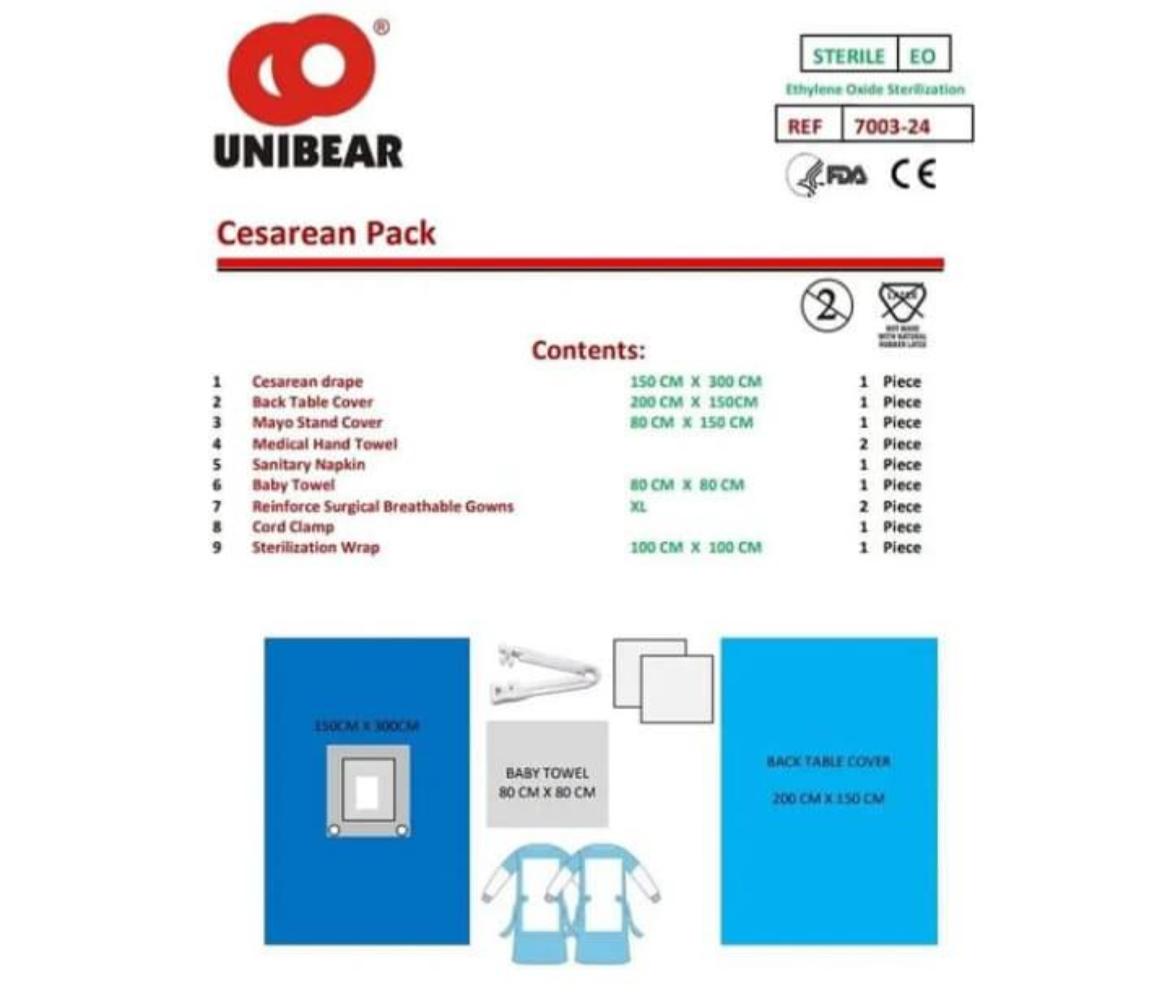

CESAREAN PACK

CESAREAN PACK